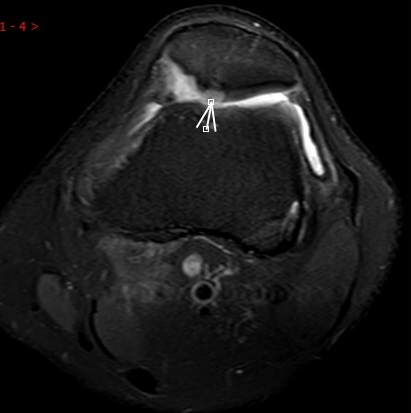

4. 不明腫脹+發(fā)熱——滑膜的“洪水警報”

場景:膝蓋腫成“發(fā)面饅頭”,皮膚發(fā)燙如“小火爐”

MRI偵查:鑒別痛風性滑膜炎、感染或類風濕病變,阻止“炎癥風暴”

(滑膜增厚、積液)

5. 夜間持續(xù)性鈍痛——骨骼的“暗夜低語”

場景:無外傷卻夜間痛醒,膝蓋仿佛“壓著巨石”

MRI偵查:篩查骨腫瘤、骨髓水腫(X線看不見的“內(nèi)傷”),警惕“沉默殺手”

(骨髓水腫)